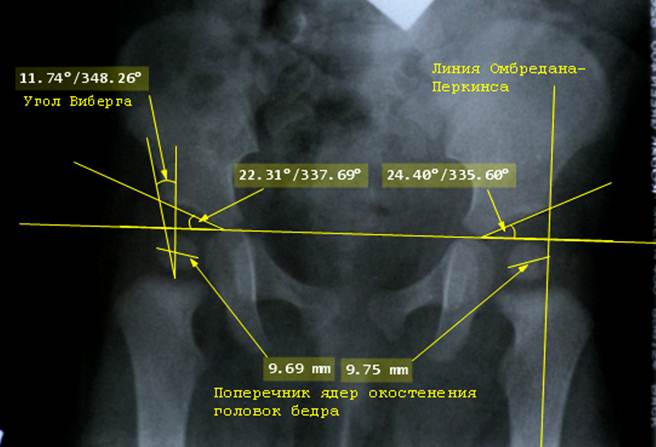

Если

на снимке видны тени ядер окостенения головок бедер, то их поперечник должен

быть измерен, а также отмечена структура ядра окостенения и его форма. В норме

ядра должны быть округлой или овальной формы, однородной структуры и

одинакового размера с обеих сторон.

Затем

проводят линию Омбредана – Перкинса: это перпендикуляр к линии Хильгенрейнера,

который идет через крайнюю наружную

точку крыши вертлужной впадины и продолжается вниз, до уровня теней

бедренных костей. Ядро окостенения головки бедра должно находится кнутри от

линии Омбредана – Перкинса. Направляясь вниз, линия Омбредана - Перкинса должна

проходить по центру или кнаружи от тени бедренной кости.

У

детей в возрасте 1 года возможно начертить угол Виберга (center edge angle). Для этого надо определить

центр головки бедренной кости. В подавляющем большинстве случаев центр

находится на нижнем полюсе ядра окостенения головки. Затем из точки центра

головки бедра проводится перпендикуляр к линии Хильгенрейнера и линия к точке

на краю крыши вертлужной впадины, через которую проведена линия Омбредана -

Перкинса. Угол между линиями и будет углом Виберга, который характеризует

костное покрытие головки бедренной кости. Костное покрытие важно для того,

чтобы человек мог ходить. Именно тот сектор крыши вертлужной впадины, который

отсекается углом Виберга, несет на себе вес туловища. Следовательно, чем угол

меньше, тем больший вес приходится на единицу площади крыши впадины и головки

бедра. И тем хуже, потому что перегруженный сустав будет разрушаться. У детей в

возрасте года угол Виберга должен быть обязательно больше нуля. В возрасте

после года, когда ребенок начинает ходить, угол Виберга прогрессивно

увеличивается.

Снимок

таза здорового ребенка в возрасте 8 месяцев расчерчен по схеме Рейнберга. Отчетливо видны большие и одинаковые ядра

окостенения головок бёдер, угол Виберга уже имеет достаточно большое

положительное значение, он отмечен на стороне правого сустава. На стороне

левого сустава проведена линия Омбредана – Перкинса, она проходит кнаружи от

центра головки бедра, обозначенного ядром окостенения её головки, и идет по центру его диафиза, как и положено

в норме.